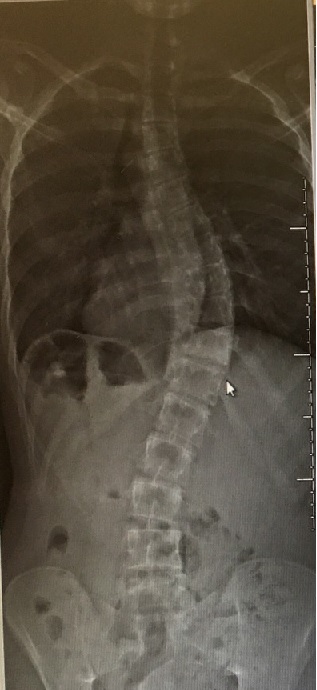

And here's a couple "after" shots:

Holy crap!  FYI those 18 screws are 45-50 millimeters long (50 millimeters is 2 inches), and 6 millimeters in diameter (about a quarter inch).  The two stainless steel rods are 12 inches in length.  Max now has two scars on his back over a foot long.  He was almost 6'2" when he went in, but we expect him to be 6'3" to 6'4" when he comes out.

He's in a lot of pain right now of course, but his prognosis is good, and we expect him to be coming home from the hospital on Friday.  He should be mostly back to normal in 6 weeks, and fully recovered in 3 months.  My wife, who is a physician, is staying with him at the hospital 24/7 and watching the other doctors and nurses like a hawk LOL!